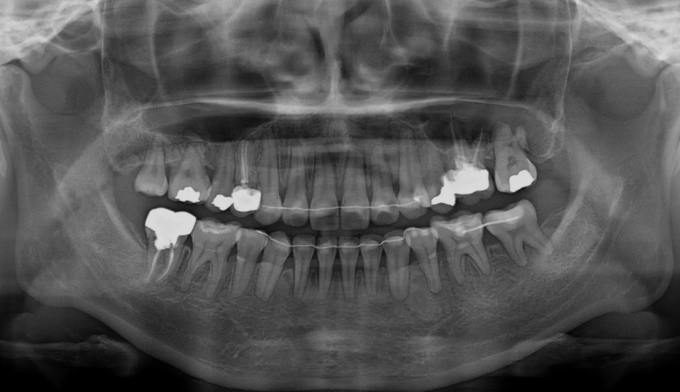

선천적으로 다수의 영구치가 상실된 경우, 이를 해소하는 방법은 공간을 벌려서 임플란트와 같은 보철치료를 받거나 혹은 교정치료를 통해 공간을 닫아버리는 방법이 있습니다. 교정치료의 기술이 부족했던 과거에는 보철치료가 주된 선택지였지만 요즘에는 교정치료를 통해 내 이를 살리면서 공간을 닫는 술식이 많이 행해집니다. 치아의 갯수가 충분해서 보철치료를 하지 않아도 되는 상황이라면 교정치료를 통해 효율적으로 교합을 형성하시는것을 추천드립니다. 교정기간은 13개월 소요되었습니다.